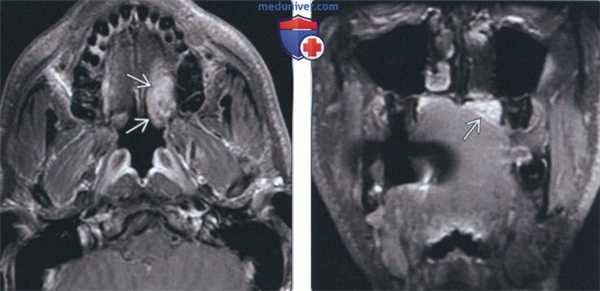

(Слева) На аксиальной КТ с КУ в подъязычном пространстве слева визуализируется большая доброкачественная смешанная опухоль овоидной формы, неравномерно накапливающая контраст. Поднижнечелюстная железа оттеснена кзади этим крупным образованием.

(Справа) На аксиальной КТ с КУ на уровне позади молярной области нижней челюсти у этого же пациента определяется опухоль и смещенная поднижнечелюстная железа. Визуализируется нормальная подъязычная железа с противоположной стороны.

(Слева) На аксиальной КТ с КУ у этого же пациента на уровне тела нижней челюсти визуализируются опухоль и смещенная ею поднижнечелюстная железа. Определяется пролабирование опухоли в просвет глотки.

(Справа) На аксиальной КТ с КУ у этого же пациента на уровне подбородочного выступа нижней челюсти визуализируется доброкачественная смешанная опухоль в подъязычном пространстве слева, смещающая подъязычную железу. На этом уровне истонченная челюстно-подъязычная мышца оттеснена кнаружи опухолью.